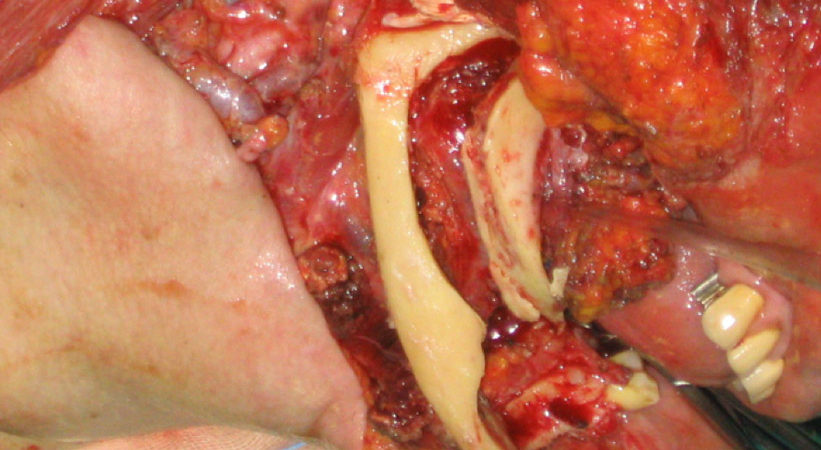

CASO CLINICO N° 2

Donna di 82 anni portatrice di un carcinoma squamoso multifocale del cavo orale infiltrante la mandibla T4N0.

Una mandibulectomia marginale è stata effettuata con tecnica piezoelettrica.